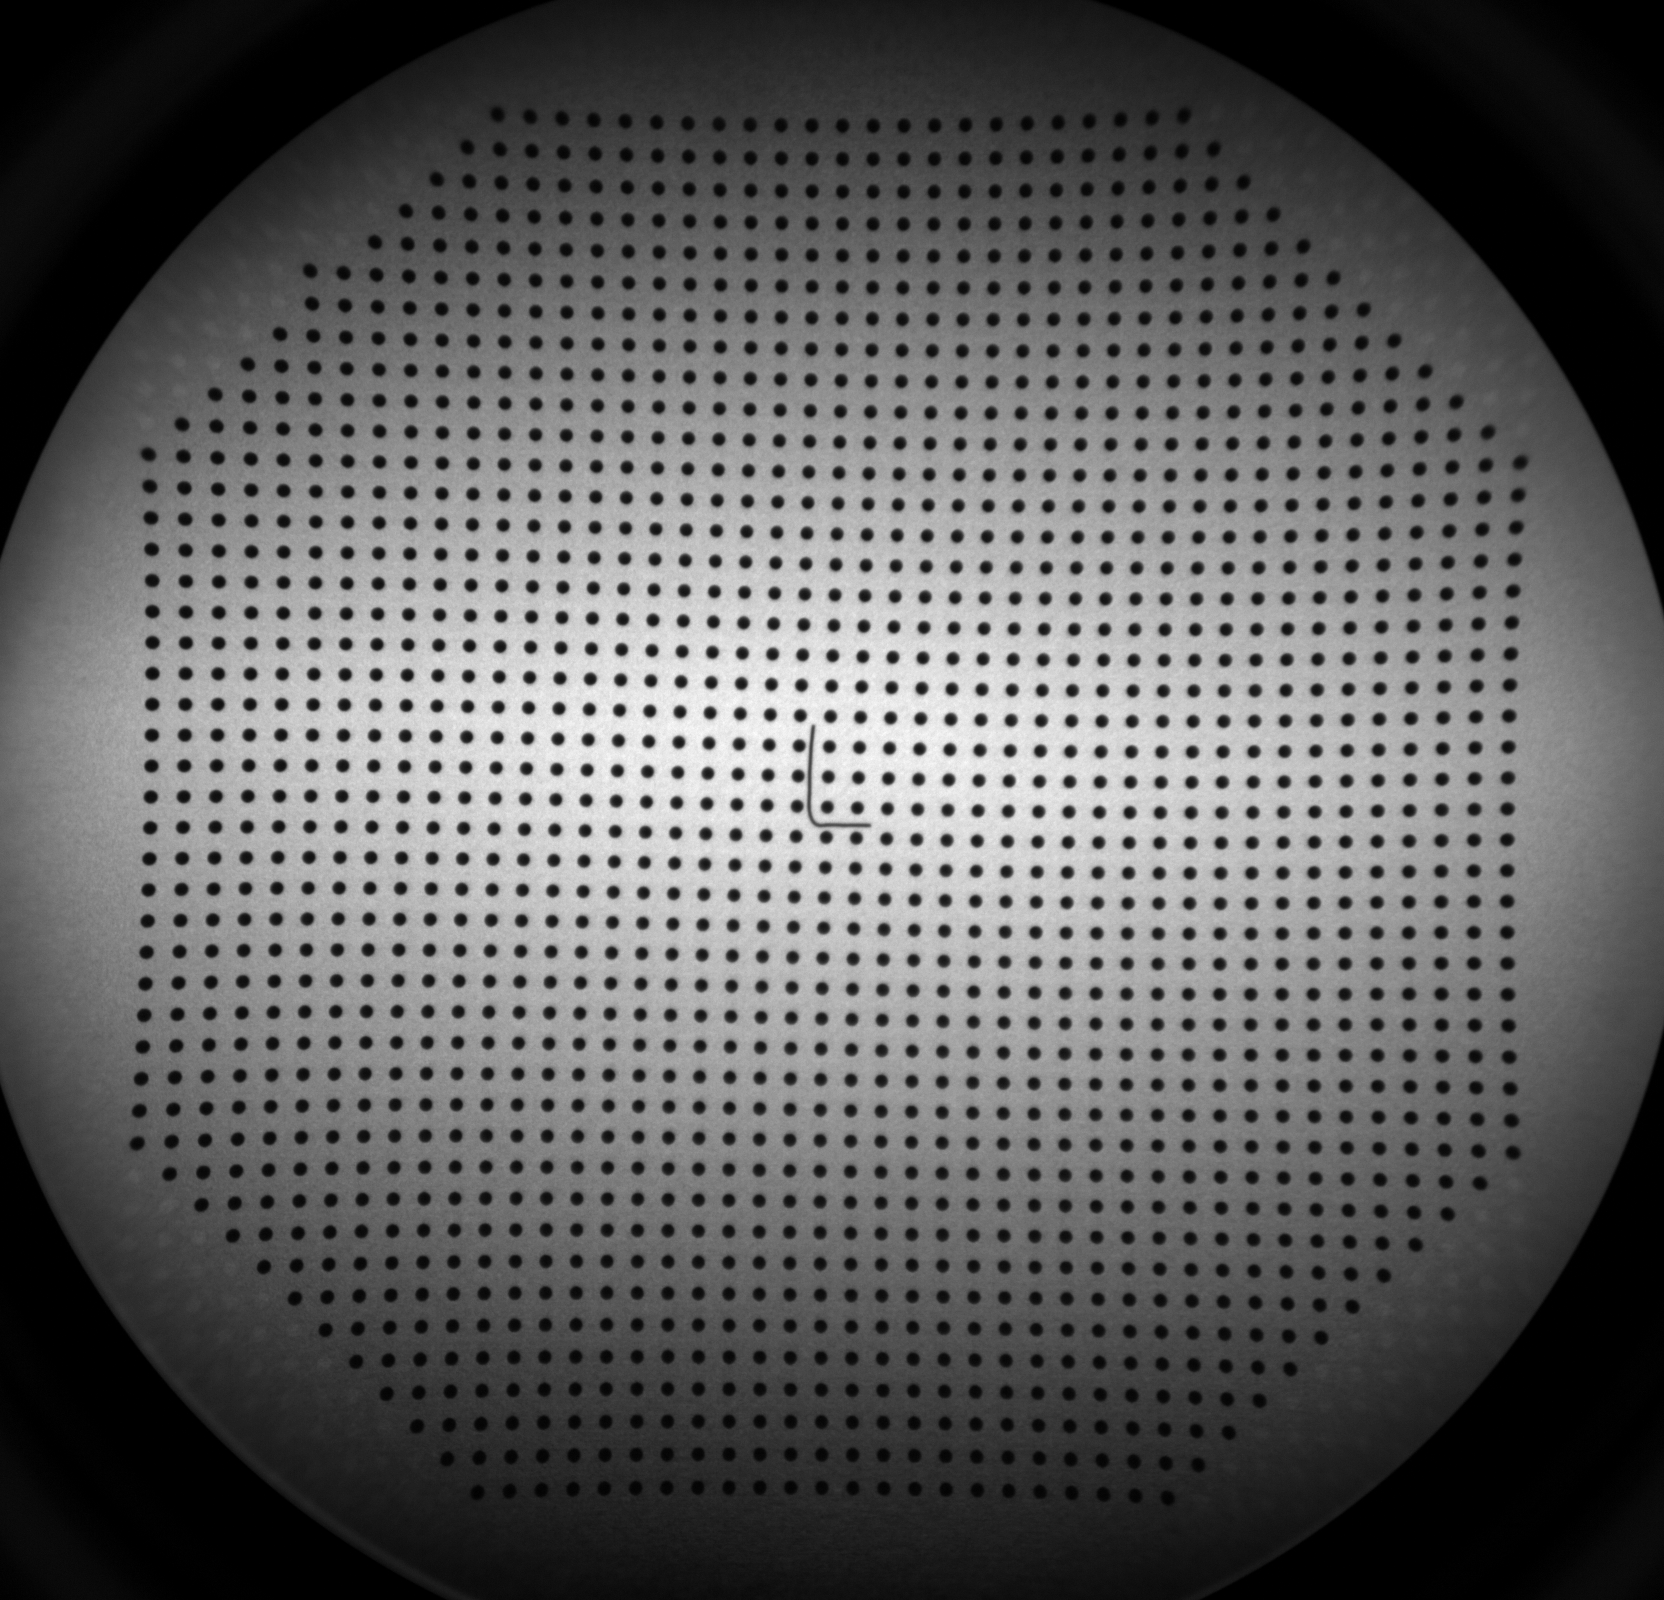

For distortion correction, a bead grid phantom (45 × 45 beads with 7 mm spacing) was affixed to the intensifier surface (Fig. 2(a)). The known geometry of the bead grid enabled precise distortion correction using a coherent point drift method to establish correspondences, followed by third-order polynomial fitting with Powell optimisation to compute the transformation.

All resulting DISCAL and SICAL values, as well as the raw distortion grid images (Fig.4(a)&4(b)), phantom measurements, and precomputed correction functions, were stored and are available within the Veriserum database. The database also includes code for computing and applying DISCAL and SICAL functions. While precomputed calibration values are available in the database for immediate application, users are welcome to reprocess the calibration parameters if necessary.

(b) DISCAL grid - Camera B